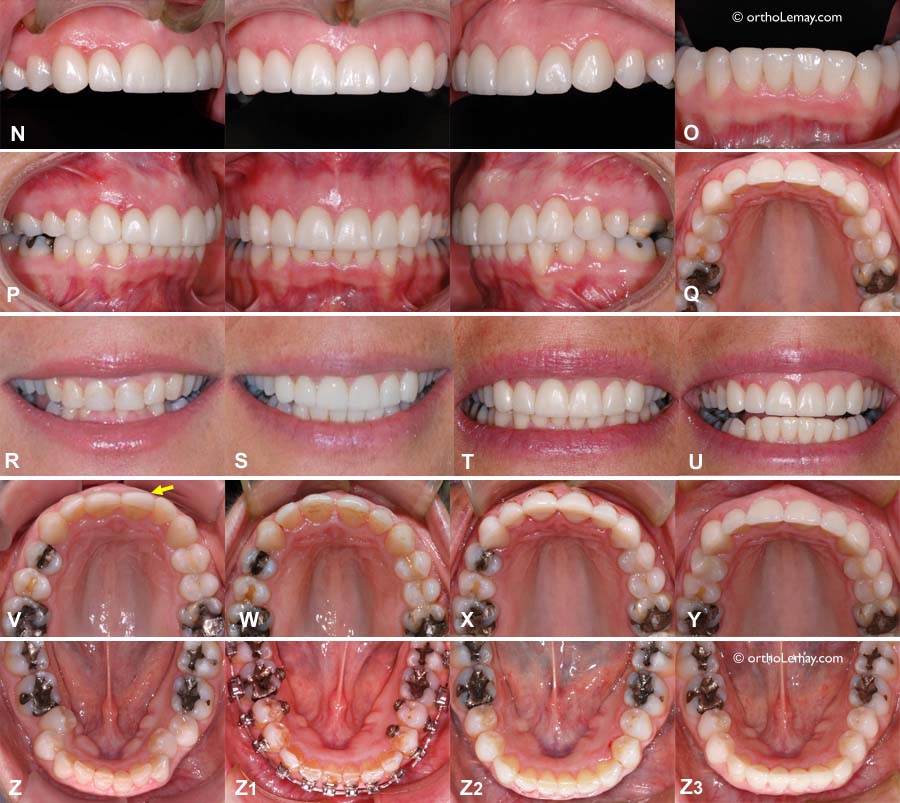

(A) Absence des 2 latérales supérieures. L’espace s’est fermé à droite et il y a un pont du côté gauche (flèche bleue). Une incisive inférieure a été extraite pour aligner les dents du bas (flèche jaune).

(B) Fin de l’orthodontie; l’espace pour la latérale supérieure droite a été ouvert et une dent temporaire a été collée sur une attelle de rétention (flèche jaune). Le pont gauche a été modifié mais est toujours en place. Une greffe de gencive a été faite pour couvrir les racines des incisives inférieures qui se sont déchaussées (flèche bleue). Des espaces sont présent entre les incisives inférieures près de la gencive.

(C) Un implant et une couronne remplacent chaque latérale (flèches jaunes), une couronne a été faite sur la canine supérieure gauche, les espaces inter-dentaires ont été comblés par le dentiste avec du composite (flèches bleues).